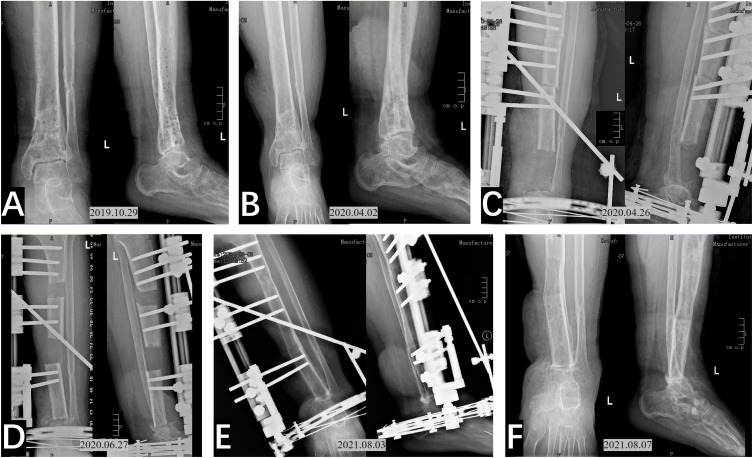

Methods: In this retrospective observational single-arm study, we analyzed the clinical data of 22 patients who had undergone multiple debridements for refractory distal tibial osteomyelitis (DTO) and had associated bone defects, and were subsequently treated with the Ilizarov bone transport technique. Following debridement surgery, bone transport treatment was administered. Regular X-ray examinations, rehabilitation guidance, and follow-up were conducted to assess infection control, bone healing, limb function recovery, and complications. Therapeutic effects were evaluated using the Association for the Study and Application of Methods of Ilizarov (ASAMI), Visual Analog Scale (VAS) score, Activities of Daily Living (ADL) score, and American Orthopaedic Foot & Ankle Society (AOFAS) score improvement.

Results: The mean follow-up was 29.32±20.92 months, with an average of 3.77±1.83 debridements. All bone defects healed, though 5 patients later required ankle arthrodesis. Complications included pin tract infection (n=10), axial deviation (n=3), ankle joint stiffness (n=2), non-union at the docking site (n=2), and delayed consolidation (n=2). At the last follow-up, ASAMI bone results: 15 excellent, 5 good, 2 poor (90.9% superiority rate). ASAMI functional results: 6 excellent, 14 good, 1 fair, 1 poor (90.9% superiority rate). VAS decreased from 4.86±0.83 to 0.5±0.66 (p<0.001). ADL improved from 80 (78.75-85) to 92.5 (90-95) (p<0.001). AOFAS score increased from 32 (25-38.25) to 82 (77-87.5) (p<0.001), with an 86.4% overall superiority rate.

Abstract Image